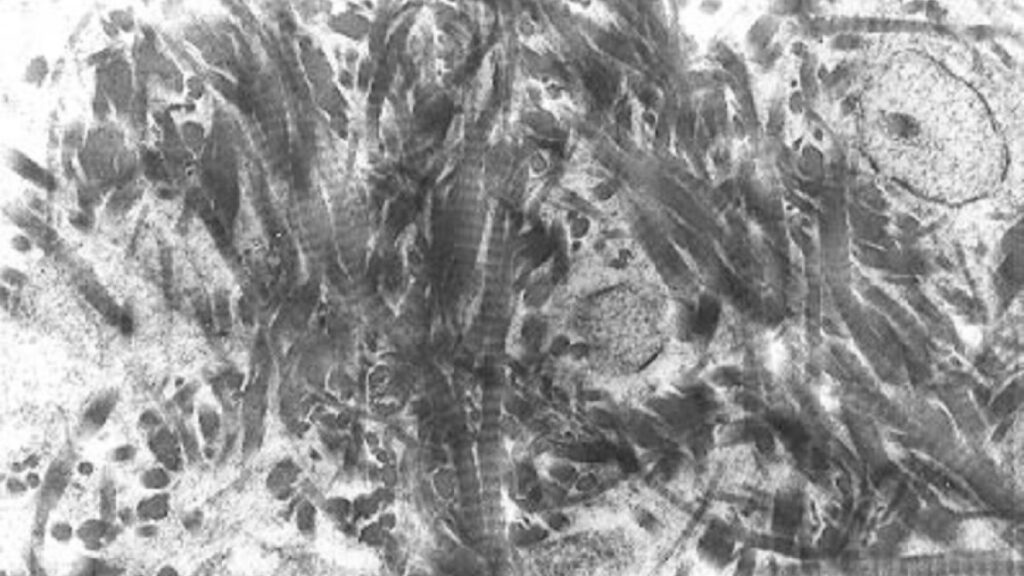

Organización fisicoquímica de la matriz ósea

La matriz ósea puede entenderse como un material compuesto natural cuya eficacia mecánica deriva de la integración íntima entre fases orgánicas e inorgánicas. A diferencia de los materiales homogéneos, en…